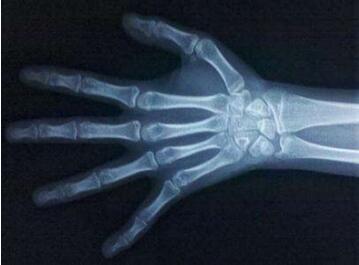

孩子测骨龄偏大的原因有哪些?孩子骨龄偏大,也就意味着孩子骨龄提前,超越年龄,而骨龄偏大则骨骺线闭合的时间也会比较早,就意味着孩子生长发育的时间和空间都缩小了。而孩子的骨骺线一旦完全闭合,也就意味着孩子的身高将终止增长。那孩子骨龄偏大是什么原因引起的呢?请看,孩子骨龄偏大的原因!

骨龄与实际年龄成正比,基本会一致,但也会有偏差,骨龄与实际年龄偏差1岁以内属正常。而如果孩子骨龄偏大于1岁,则可能是身体疾病所致,影响到骨骼异常发育,如肾上腺皮质增生症或肿瘤、Alreb-ert综合征、甲亢、卵巢颗粒细胞瘤等将导致骨龄提前,要请医生检查,对症治疗。

儿童的骨龄与实际年龄偏差1岁以内属正常,如果孩子没有疾病,只是骨龄偏大,可以通过调整饮食、运动和睡眠帮助孩子恢复到正常骨龄,让孩子达到理想身高。如果骨龄大大超过实际年龄,则可能是性早熟、肾上腺疾病等引起,应请医生对症治疗。

[学龄前健康]儿童身高的增长主要取决于骨骼软骨细胞的不断增殖骨化生长,从而使骨骼延长,实现身高的增长。 因此,与年龄相比,骨龄能更好地反映儿童生长发育的情况,判断儿童身高是否符合标准,